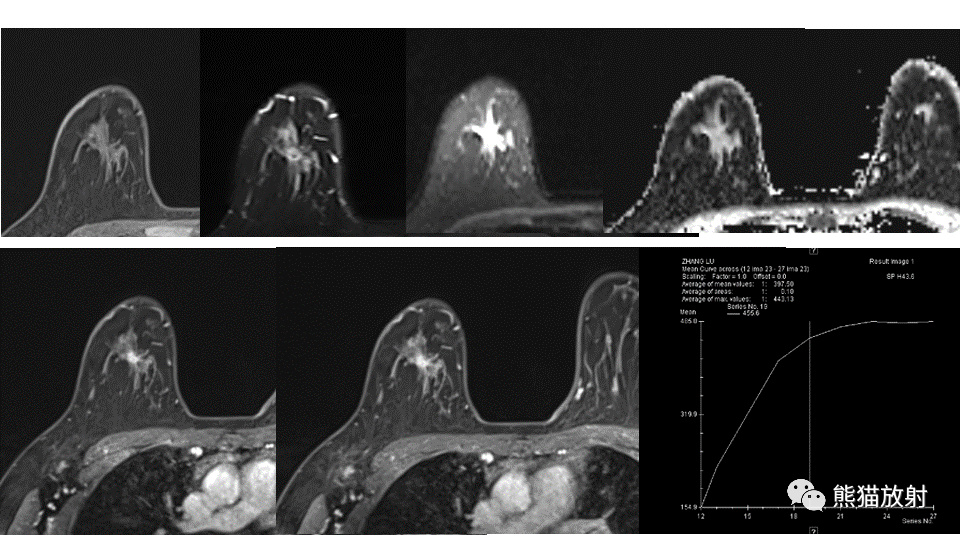

【病例】纤维囊性乳腺病伴纤维腺瘤形成 VS 乳腺增生病并间质硬化-1

【病例】纤维囊性乳腺病伴纤维腺瘤形成 VS 乳腺增生病并间质硬化-2